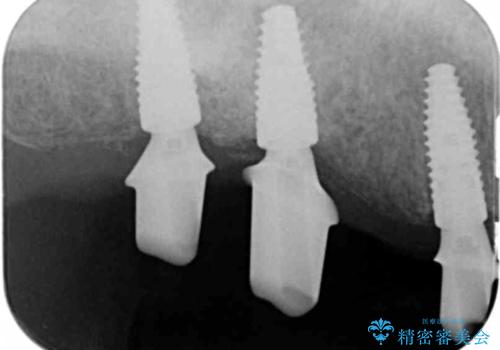

重度に吸収してしまった歯槽骨をしっかりと造成を行ったのちにインプラント治療を行ったので、安定した歯周環境にすることができました。